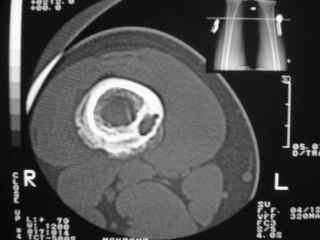

Анамнез практически никакой: в следствие травмы (растяжение связок коленного сустава) от 07.11.2004 выполнены Rg-граммы в травмпункте и обнаружено опухолевидное образование. Первичные Rg-граммы я не публикую, так как они заметно худшего качества, да и динамики за прошедшие три недели не отражают. Болевой синдром купирован в течение трёх дней. В настоящий момент мальчика ничего не беспокоит. Ходьба не нарушена, опухоль пальпируется с трудом по задней поверхности в н\3 правого бедра, пальпация безболезненна, объем движений в суставах правой нижней конечности полный и симметричный. Кожа над опухолью не изменена.В нашей клинике проведено дополнительное обследование: общие анализы крови и мочи, биохимия крови без особенностей. Выполнены Rg-граммы на цифровом Siemens обычные и продольные томограммы срезами 3-5 мм, а также компьютерная томография поперечными срезами по 5 мм. Прошу обратить внимание, что на приведённых томограммах видны две полости 10х15 мм и 15х60 мм. Также имеются два опухолевидных образований наслаивающихся друг на друга: уплощённое и вытянутое 10х100 мм и элипсовидной формы 15х30 мм. Это хорошо заметно на фото a_1.jpg c_1.jpg и d_1.jpg. Плотность внутри полостей 125% от плотности костномозгового канала, плотность наружного опухолевидного образования 55% от плотности кортикального слоя. Также отмечается линия перелома по центру наружного опухолевидного образования.Исходя из полученных данных мнения в плане диагноза несколько разделились от 1)сочетания кортикальной фиброзной дисплазии и латентно протекавшего маршевого перелома н\3 правого бедра до 2)остеосаркомы. В отношении первого варианта не сходится отсутствие клиники при переломе такой крупной кости как бедро, второй вариант вообще оставлю без комментария, ибо некомпетентен. Хотелось бы услышать мнения коллег, с удовольствием ознакомлюсь с любыми предположениями и замечаниями.С уважением, Александр Е. КлоковОтделение детской ортопедии и травматологииБСМП г. Мурманска.